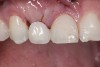

Six years later, the patient was in his fourth year of college when he finally returned for implant placement (Figure 6). Interestingly, the provisional bridge had not come loose since it was bonded, even though the patient had a nail biting habit and had fractured most of the resin-based composite on the central incisors. He had also failed to wear his retainer, and as a result, the upper left lateral incisor had rotated slightly (Figure 6). In the right lateral incisor site, there was a horizontal deficiency in the bone and overlying soft tissue. A cone-beam computed tomography (CBCT) image was taken, and the area was evaluated for implant placement. There was enough native bone to place a 3 mm implant, but a connective tissue graft was needed to rebuild the deficient ridge. Unfortunately, when the patient presented for implant placement, it was during a holiday break from school and he needed to study. Therefore, the patient did not want to simultaneously augment with a connective tissue graft at the time of implant placement due to the pain associated with treatment. A 3.0 x 10 mm Astra Tech implant was placed, and the resin-bonded bridge was rebonded, utilizing the CoJet Silica, salinization, and the same dual-cured resin cement. Four months later, the patient returned for the connective tissue graft (Figure 7). The bridge was removed, the graft was performed utilizing a tunnel technique, and the bridge was rebonded as described earlier (Figure 8). After another four months, the patient returned during a two-week break. At this time, the implant was exposed, the tissue was manipulated with provisionals, and the final restorative work was completed (Figure 10 and Figure 11).

(7.) Resin-bonded bridge after removal, implant placement, and bridge recementation.

Figure 7

(8.) Resin-bonded bridge removed and CT graft completed. Bridge recemented once more. Note reduction in cervical area of pontic.

Figure 8